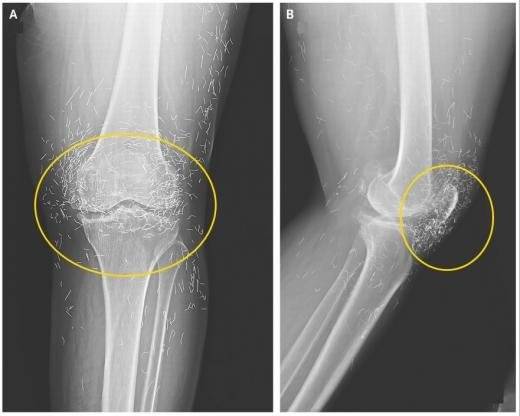

2014년 임상 의료분야 국제 학술지 ‘뉴잉글랜드 의학 저널’에 65세 한국 여성의 무릎 엑스레이 사진이 실려 금침시술에 대한 위험성을 강조하기도 했다.

해당 여성은 퇴행성 관절염이 낫지 않자 통증 완화를 위해 ‘금침 요법’을 받았다. 통증 완화를 위해 계속 침을 주입하다 보니 무릎에 박힌 침의 개수가 수백 개가 넘었다.

미국 보스턴대학 방사선과 알리 게르마지 교수는 “신체는 이물질이 들어오면 이를 제거하려는 방어 작용을 수행하기에 해당 과정에서 염증 등이 발생할 수 있다”며 “또한 침들이 몸속을 돌아다니면서 동맥과 같은 중요 부위를 손상시킬 수도 있다”고 우려했다.